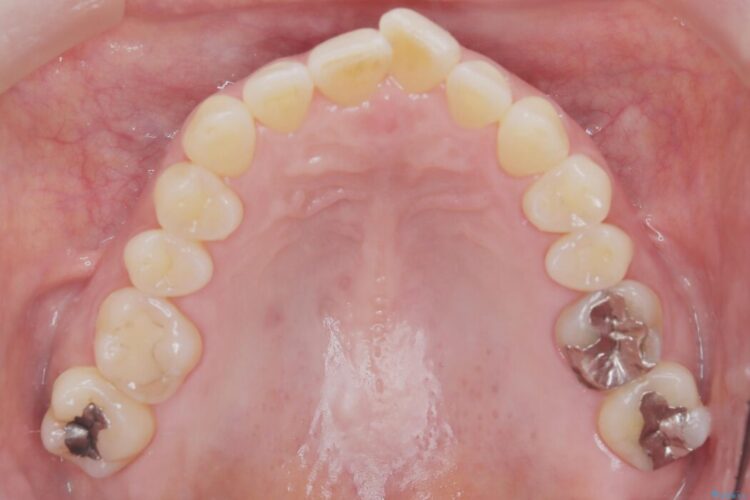

精密検査の結果、抜歯は不要、わずかなスペースを確保することで歯並びを整えられると診断しました。

スペース確保は、奥歯を少し後ろへ動かす遠心移動と、歯の側面をわずかに削るIPRを併用し、約1年間での治療完了を目指しました。